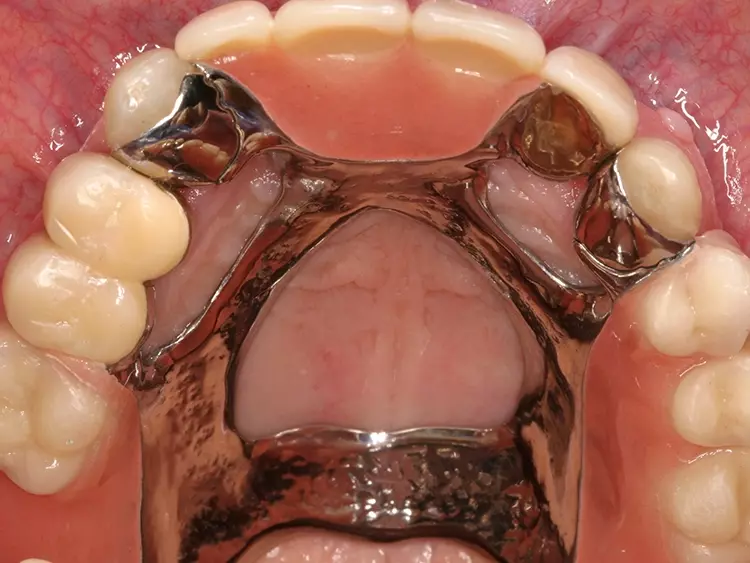

Eine Kippmeiderfunktion und erhöhte Rigidität des Flügels wird durch Gestaltung der zum Prothesensattel weisenden Approximalfläche des Attachments als parallele Anschlagplatte erreicht. Bei ausreichenden Platzverhältnissen lässt sich die Stabilität des Geschiebes zusätzlich erhöhen, indem eine orale Umlauffräsung angelegt wird (Abb. 5 und 6).

Die definitive Präparation beinhaltet eine leichte zervikale Hohlkehle und zwei approximale leicht konische Retentionsrillen. Bei Frontzähnen werden noch eine inzisale Abschlusskante, eine Noppe sowie eine leichte palatinale Veneerpräparation angelegt (Abb. 11 und 12). Bei Seitenzähnen ist eine zusätzliche okklusale Auflage zu präparieren (Abb. 13).

Zur Eingliederung wird ein Kofferdam zur absoluten Trockenlegung gelegt. Die Autoren empfehlen, vor definitiver Eingliederung das sichere Positionieren der Attachments in Endposition mit der Assistenz zu üben. Da die Flügel einen eindeutigen, retentiven Sitz haben, sind Positionierungsschlüssel nicht nötig.